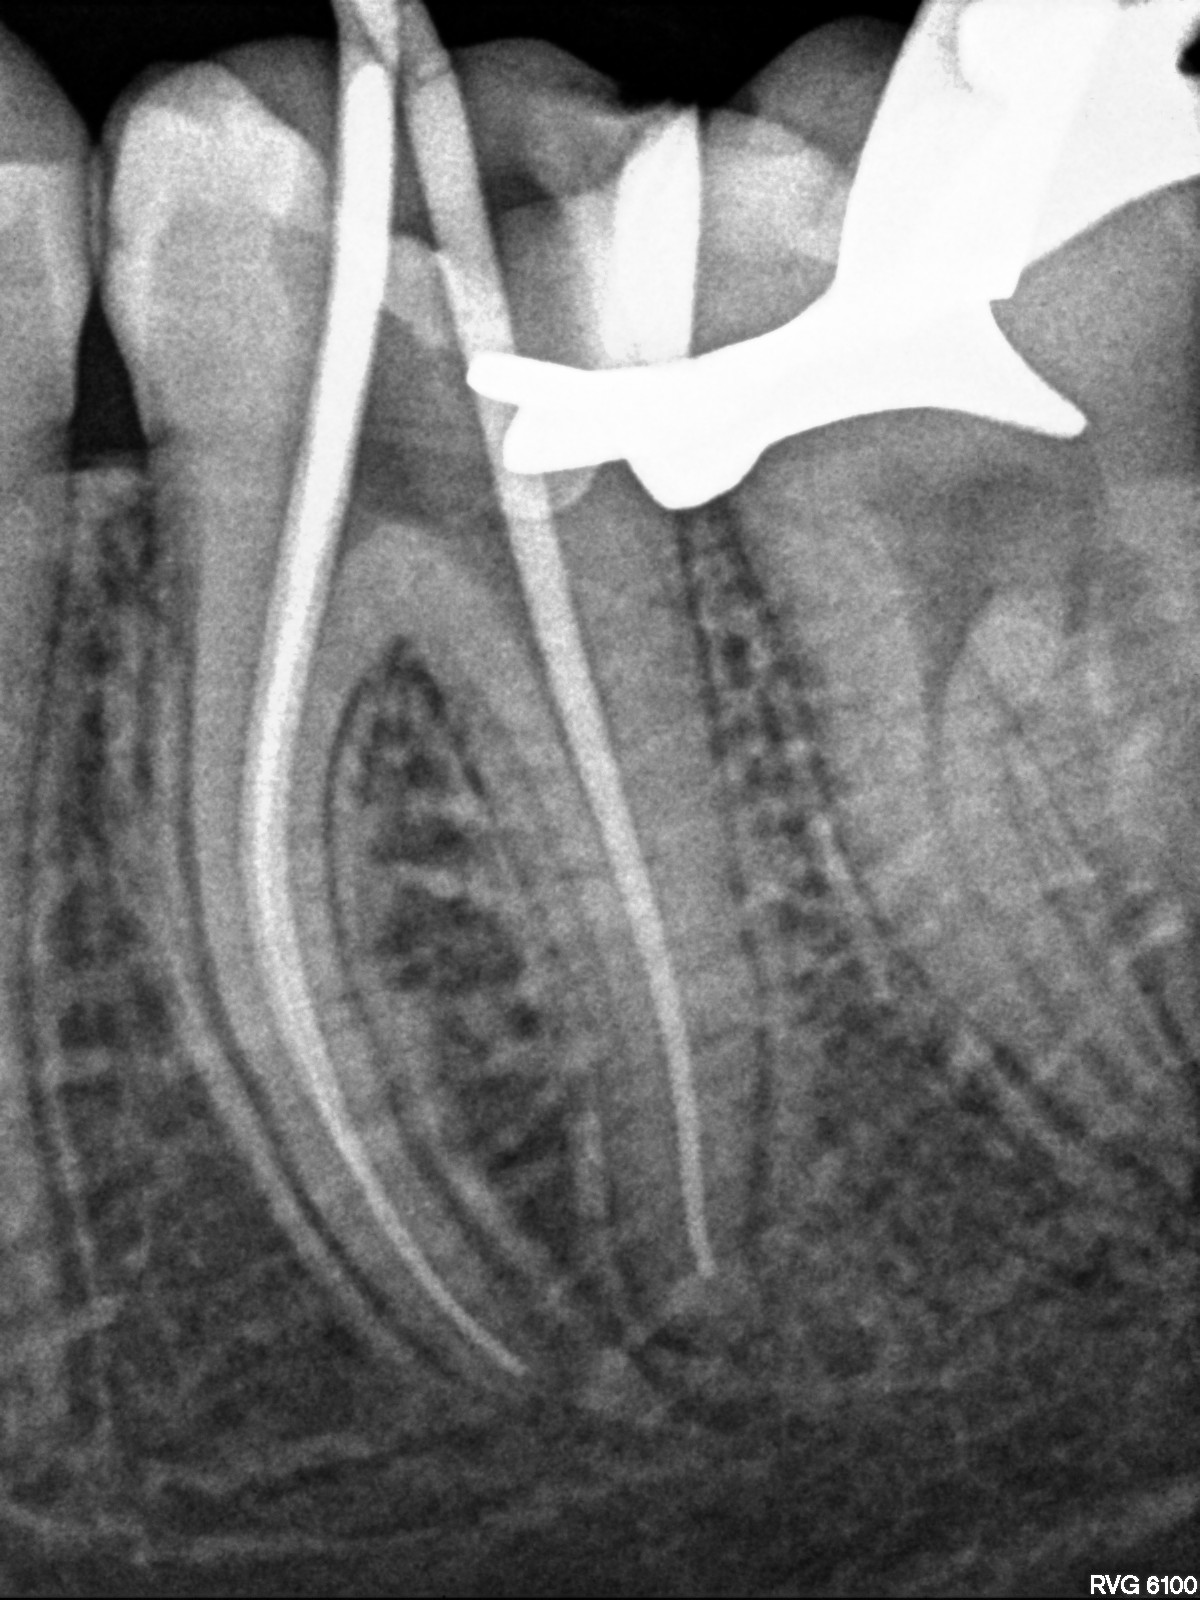

En los casos en los que una endodoncia previa no ha tenido el resultado esperado, es posible realizar una reendodoncia. Este procedimiento consiste en retirar el material de relleno anterior, localizar y tratar conductos que no fueron tratados inicialmente y aplicar un protocolo de desinfección riguroso antes de volver a sellar correctamente todo el sistema de conductos. La reendodoncia permite resolver infecciones persistentes y, en muchos casos, evitar la extracción, conservando el diente natural y mejorando su pronóstico a largo plazo.

Imágenes: Reendodoncia en un molar inferior derecho